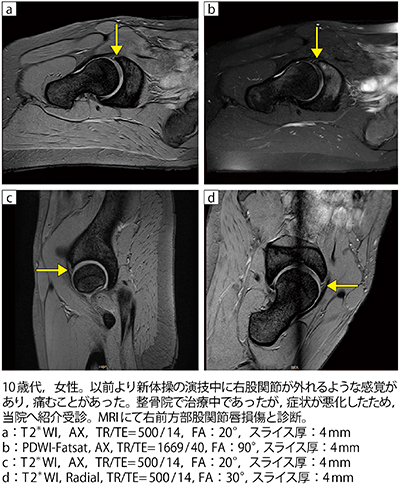

■症例2:右前方部股関節唇損傷